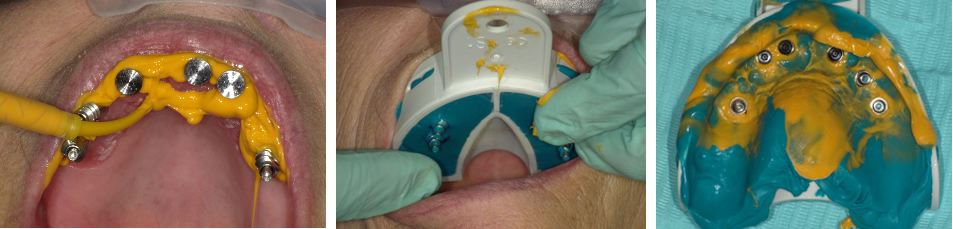

Four months later, overdenture attachments that permitted angle correction up to 60 degrees were attached to the implants by using a hex driver and were torqued per the manufacturer's recommendation (Figure 11).41 The attachments had a small screw-access hole that prevented food entrapment. Attachments are available in various heights.41 The height of each attachment should be predetermined by measuring the distance between the platform of the implant and the crest of the peri-implant tissue (Figure 12).47

Fig 11. Overdenture attachments attached to the implants (LOCATOR R-Tx, Zest Dental Solutions).